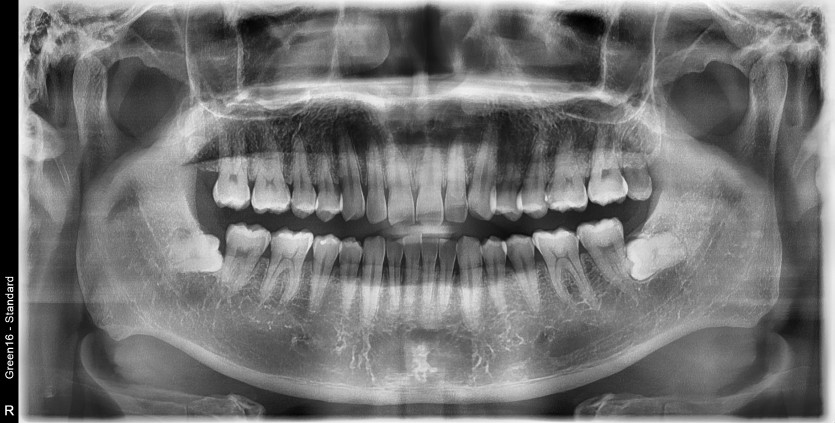

#28,38 사랑니 발치

구강 외과 전문의가 당일 발치했습니다.